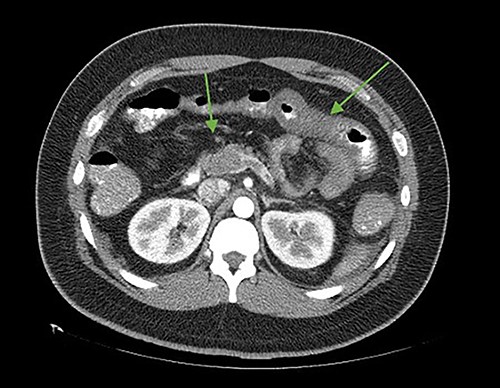

On the seventh postoperative day, he began with abdominal pain, tachycardia, fatigue, and anorexia, limited fluid intake and minimal ambulation. On the eighth day, the patient presented to the emergency department due to intolerance to oral feeding, acute abdominal pain (VAS 8/10), in antalgic position, tachycardic and diaphoretic. Physical examination revealed abdominal hyperalgesia and hyperalgesia. Laboratory tests revealed hemoglobin of 11 g/dl, 18 700 leukocytes (95.3% neutrophils), C-reactive protein of 13.3 mg/dl. Blood gases with pH 7.42, lactate 1.6 mmol/L. A contrast-enhanced abdominopelvic tomography showed portal, mesenteric, and splenic vein thrombosis associated with jejunal wall thickening with adjacent mesenteric changes and free fluid in the cavity (Figs 1 and 2).

Axial cut. In the arrows, there is a lack of splenomesenteric opacification towards the posterior part of the pancreas and striation of the adjacent peripancreatic fat. Edematous intestinal walls in the jejunum, free fluid in the left paracolic gutter.